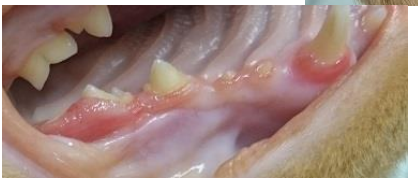

tooth resorption at the stage of healing where the crown has already fallen off and the gingiva has healed over leaving a faint bump where P3 used to be